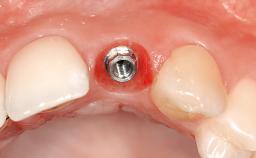

| Case Type | Single-Tooth Space |

| Jaw | Maxilla |

| Area | Anterior |

| # of Teeth | 1 |